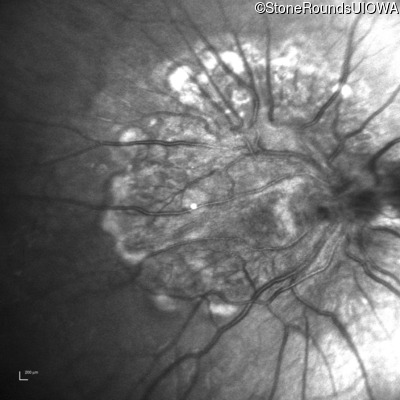

This 9 year old male was noted to have some crossing of his eyes at 2 months of age and the eye exam which followed identified a retinal lesion in the right eye. When he was six years old an epiretinal membrane was noted in his left eye. Two years later it was decided that it was a thin hamartoma in that eye as well. He underwent neuroimaging at age 7 which identified bilateral acoustic neuromas.

| Age at visit: 8 years |

| Age at visit: 10 years |

| Age at visit: 11 years |